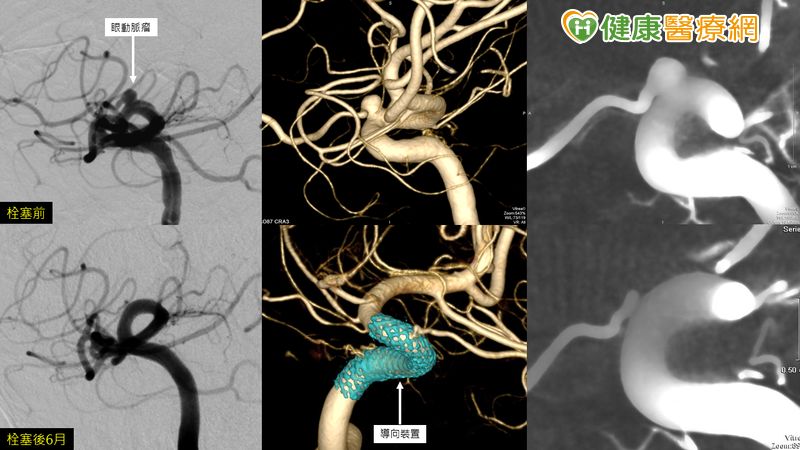

林口長庚紀念醫院放射診療部主任、中華民國放射線醫學會理事及台灣神經血管外科與介入治療醫學會理事長黃浩輝教授對此解釋,劇中主角用的是傳統白金線圈栓塞手術,栓塞過程的確可能使眼動脈出口被堵住導致失明,但近年來有更新的方法利用血流導向裝置治療動脈瘤,置放後可使腦動脈瘤萎縮甚至消失,眼動脈不會被阻塞,可避免劇中治療的困境上演。黃浩輝教授也分享,自己臨床中遇過極度相似的案例,置入血流導向裝置治療後的病患追蹤到現在,除動脈瘤已完全塞閉外視力也沒有受到影響,預後相當良好。

▲眼動脈瘤

黃浩輝教授解釋,血流導向裝置是利用質地軟、緻密的軟金屬線編織的密網支架,放入血管腔內而非腦動脈瘤囊,從血管腔中導流血液,同樣有避免血液流入動脈瘤囊內的效果;再來,隨著時間,血流導向裝置可促進血管內膜化,達到保護血管壁,甚至有讓腦動脈瘤萎縮的效果,降低復發機率,也同時減少腦動脈瘤壓迫到其他神經的機率。

黃浩輝教授指出,國際大型研究結果顯示,患者置入血流導向裝置五年後,動脈瘤完全閉塞率高達95%,而不只小型動脈瘤,對大動脈瘤也有相當程度的功效。